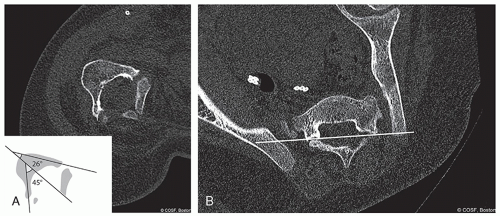

Computed tomography (CT) scan (Figure 5.1A and B)

Determination of bony anatomy

Planning for anchor placement (profile and orientation)